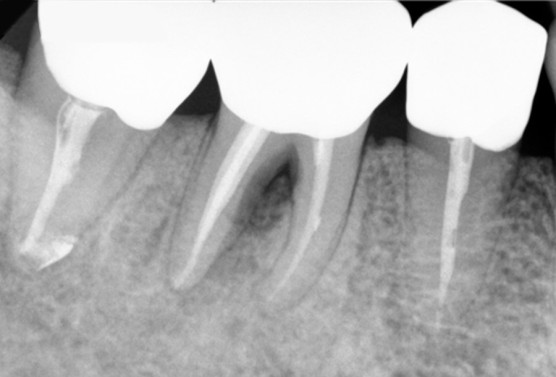

[2021. 09. 08 초진]

두치아 모두에서 뿌리끝 염증이 보이며, 오른쪽 치아에서는 뿌리와 뿌리 사이, 가랑이 부분까지도염증이 생겨 어둡게 보이고 있습니다.

이럴 경우 먼저 신경치료를 해서 뿌리끝 염증을 다스리고,  추가적으로 잇몸치료를 동시에 진행해서 염증을 다스려줍니다.